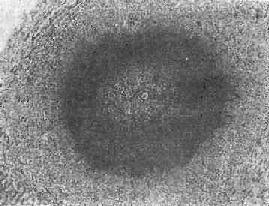

图19-5 肝血吸虫病之急性虫卵结节

结节中心有一成熟虫卵,卵壳表面可见放射状物质,周围广泛坏死伴大量嗜酸性粒细胞浸润